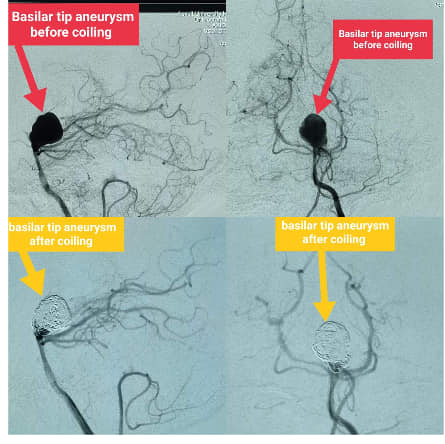

Coiling of large  basilar tip aneurysm

تم إنهاء إجراءات التأمين الصحي و عمل دخول للمريض بالقسم الخاص بالمستشفيات الجامعيه وتجهيزه لغرفة العمليات لعمل قسطرة مخية وتحت تخدير كلي عن طريق الشريان الفخذى ثم الوصول للشريان الفقرى الايسر وتم وضع ٤ ملفات حلزونية و٣ ثلاثية الابعاد ذاتيه الانفصال.

تم عمل قسطرة بعد انتهاء تركيب الملفات للتأكد من الغلق التام وعدم تأثر اي شريان من الشرايين المتجهه للمخ والمخيخ ثم وضع المريض بغرفة الافاقة بوحدة القسطرة وبعد تعافيه تم نقله للعناية المركزة المجهزة مسبقا فقط للمتابعة وبدون اي مضاعفات والمريض بحالة جيدة ومستقرة وبفضل الله وأطبائنا الكرام تم شفاء المريض وعاد الي منزله سليم معافي .